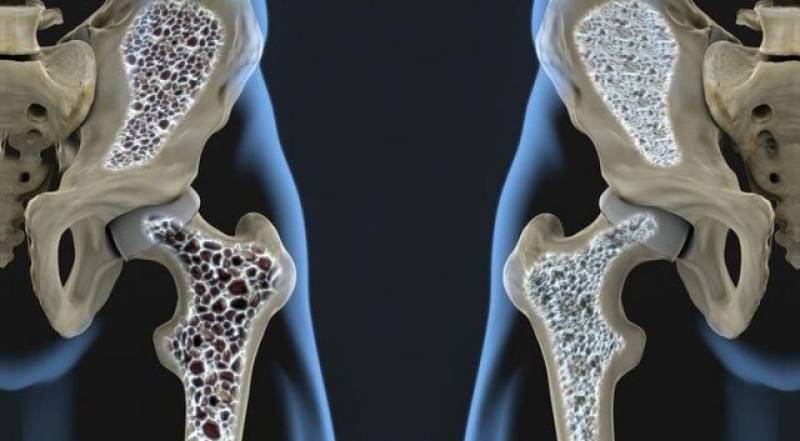

وقتی استرس شبیه سرماخوردگی میشود